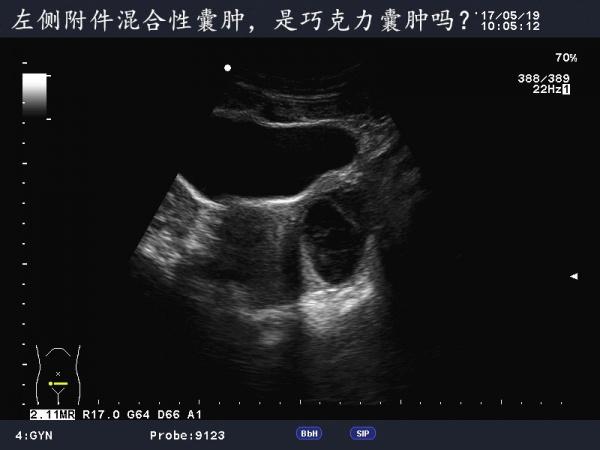

这是巧克力囊肿吗?

患者女,40Y,因下腹部疼痛就诊,最近一次月经来潮量少且疼痛厉害,以往基本上正常。

于月经第11天行B超检查。

不是很典型的巧克力囊肿,可以随访复查看看

可定期复查,黄体不除外